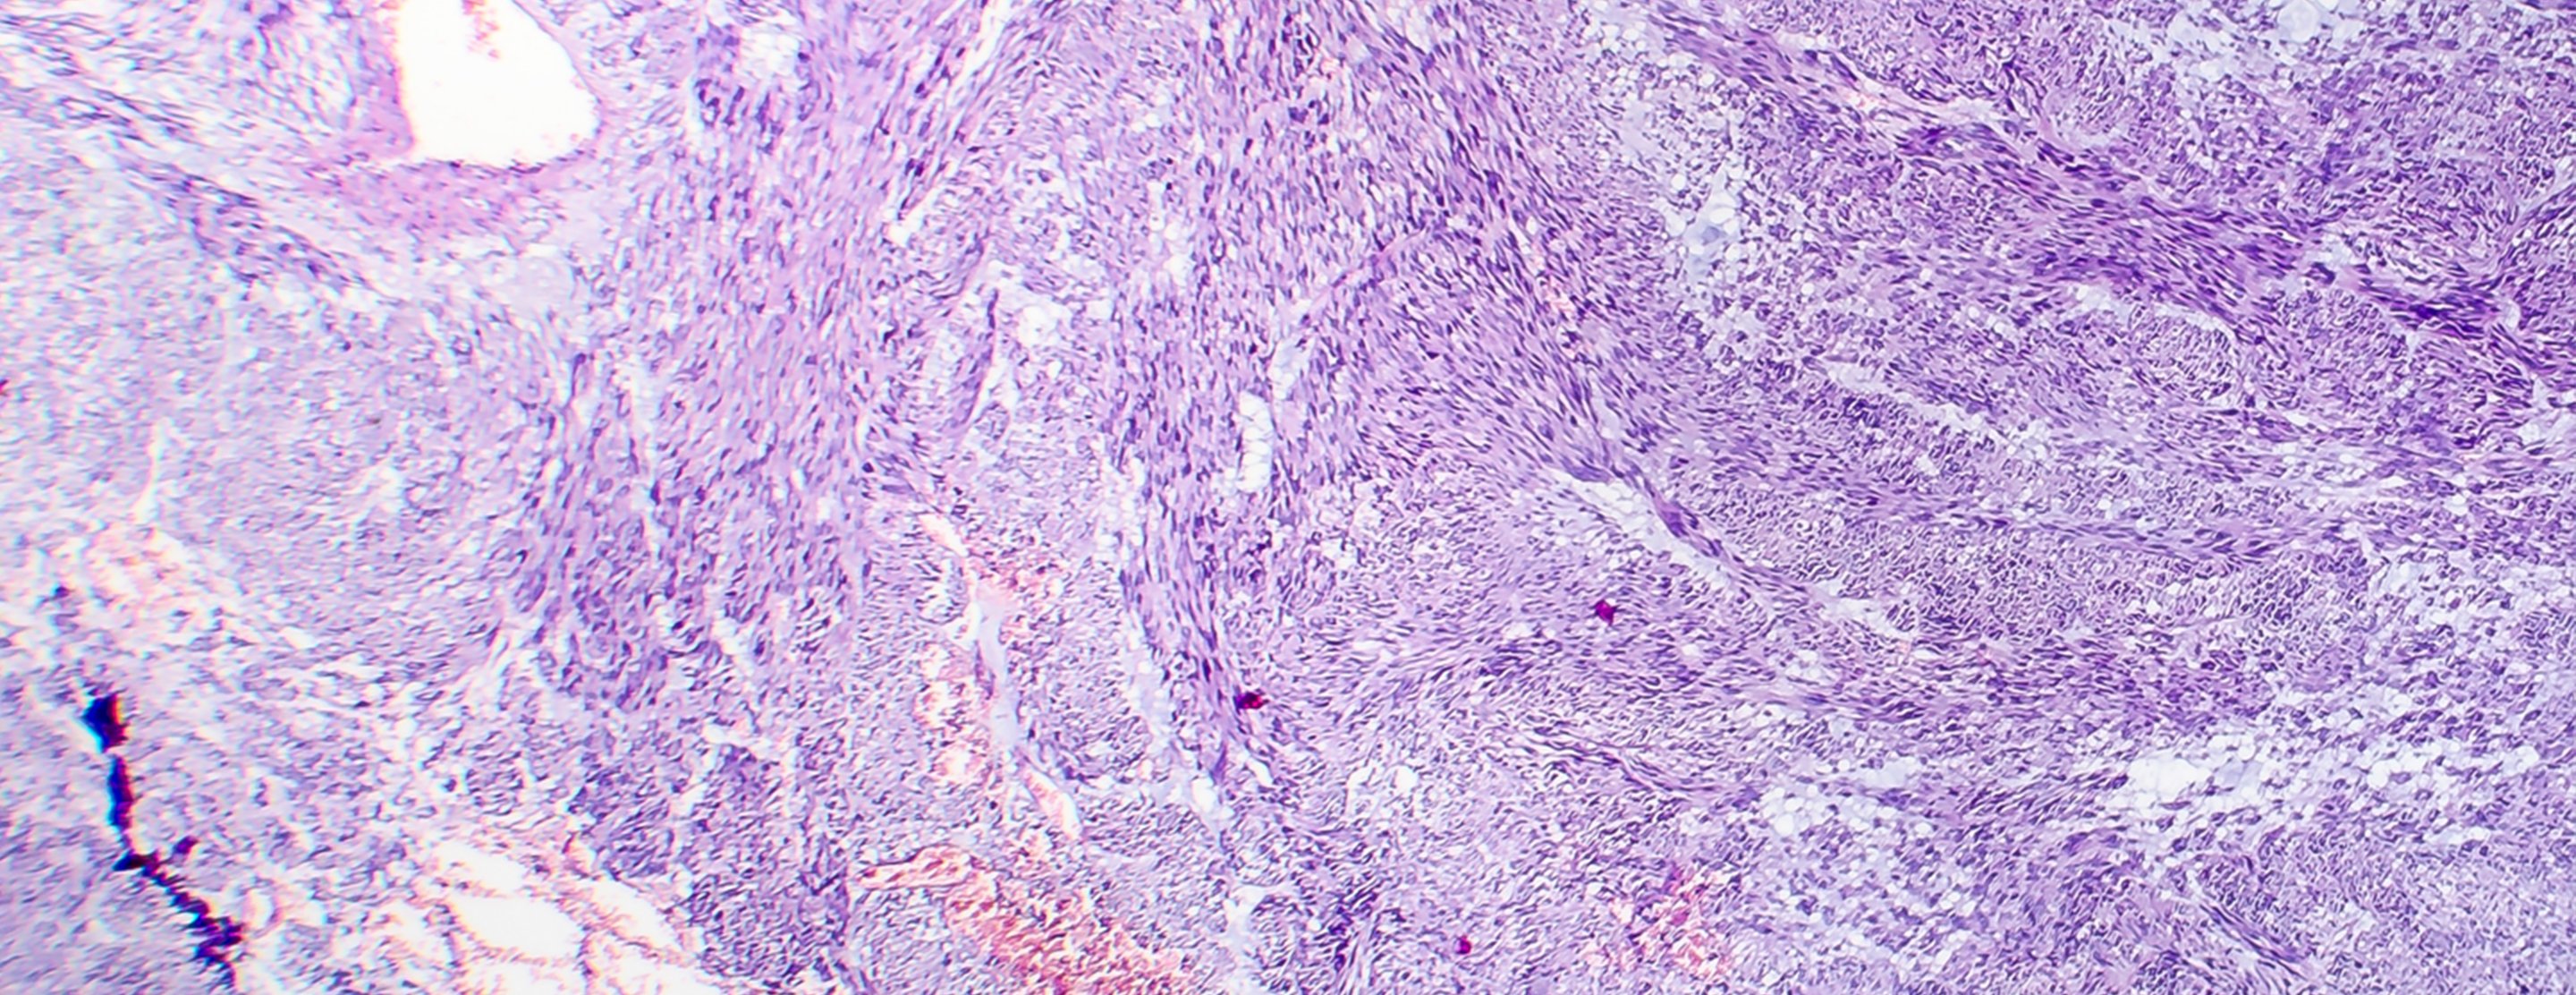

Fibroids are round muscle growths that develop within a woman's uterus, also known as the womb, which is a pear-shaped organ located between the bladder and rectum.

Fibroids are almost always benign, meaning that they are non-cancerous. Fibroids vary in size, ranging from as small as a pea to as large as a melon. They are also called leiomyomas or myomas.